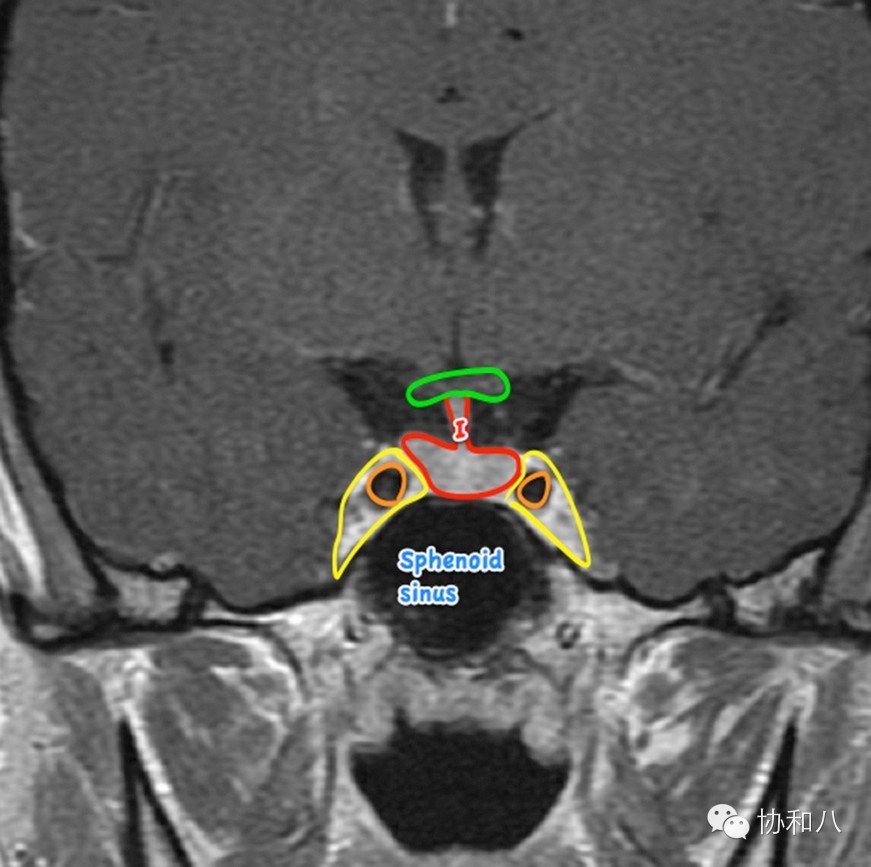

B.冠状位MRI T1W1

绿圈-视交叉;红圈-垂体柄+垂体;黄圈-双侧海绵窦;橘红色圈-双侧颈内动脉;sphenoidsinus-蝶窦。